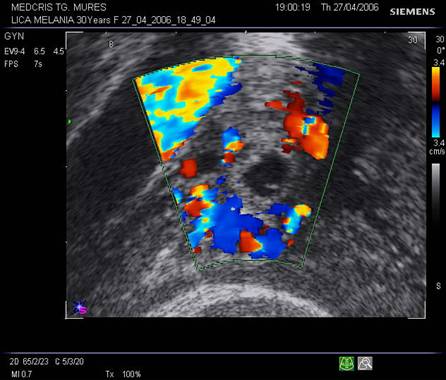

Fig nr58

Sac ovular intratubar ampular ( dg. complet doar laparoscopic, aici cu sageata ) cu imagine

caracteristica de coroana trofoblastica bine vascularizata la exam doppler

color . Alaturi se remarca ovarul drept cu corp galben, tot cu ecou hipoecogen

central ( marcat cu doua sageti )